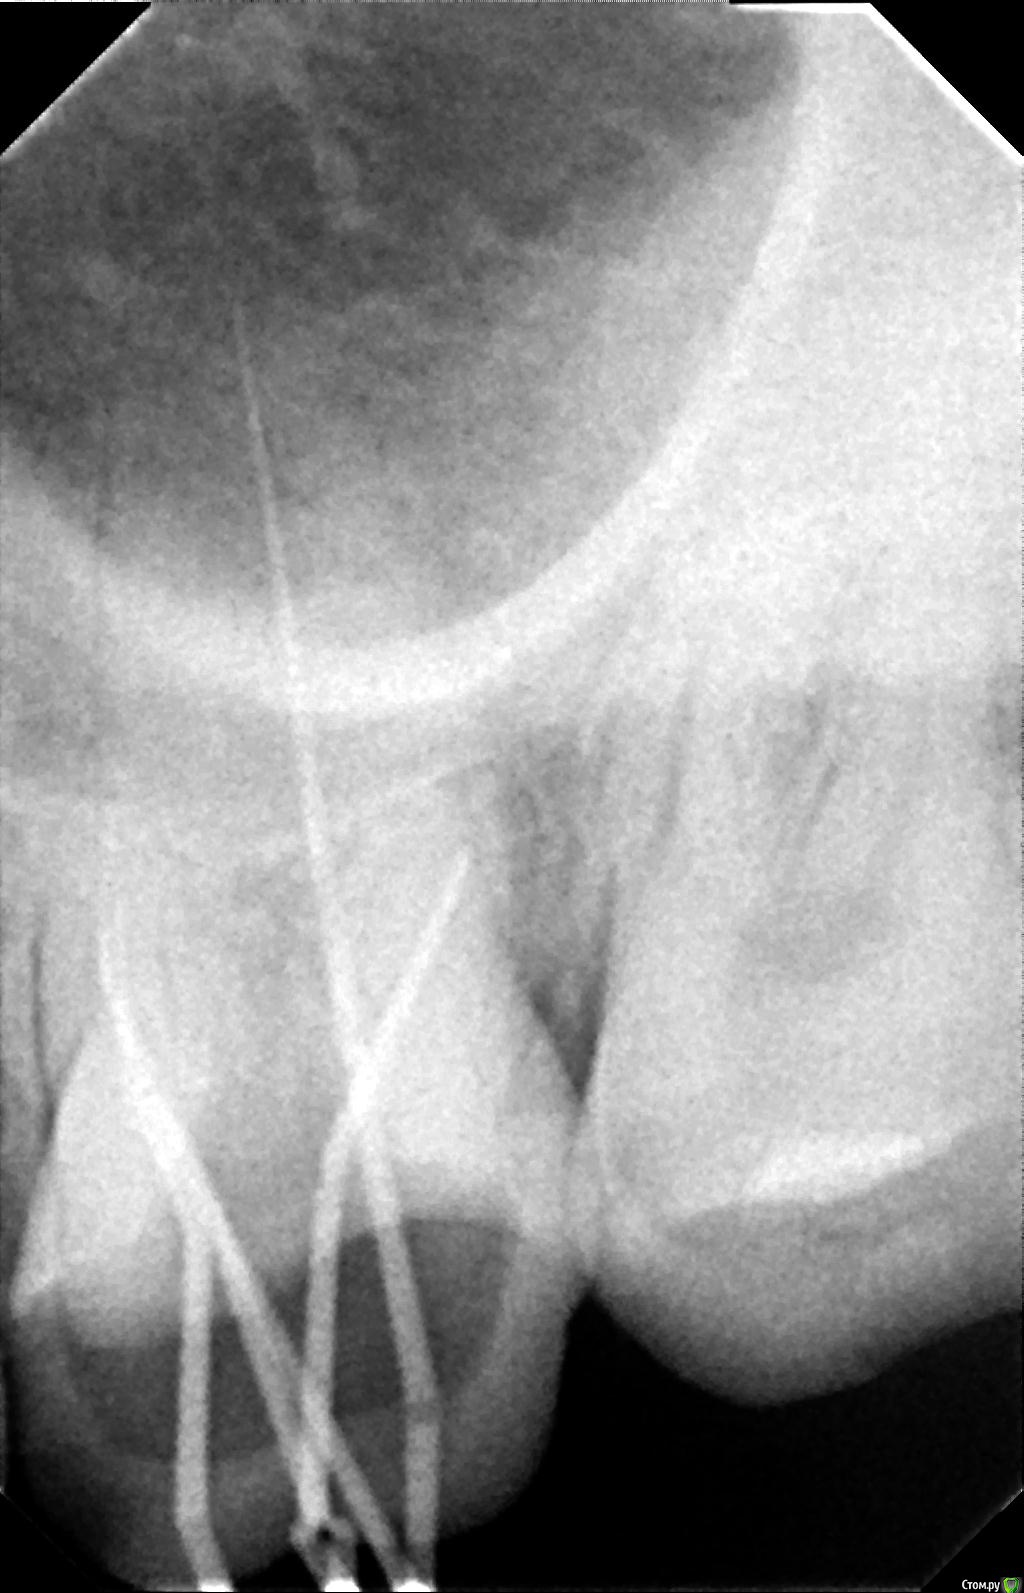

К сообщению прикреплены фотографии процесса лечения 26-го зуба.

После пломбировки каналов, я решил пойти ставить коронку в другую клинику, но там мне сказали, что не дают гарантию на этот зуб, поскольку каналы не долечены, и что я могу обратиться по гарантии в первую клинику. Но в первой клинике мне сказали, что все долечено. Хочу узнать мнение специалистов по этому поводу. Должен ли канал очищаться и пломбироваться до самой границы корня? Видно ли, что зуб не долечен по этим снимкам?

Так же в первой клинике в процессе лечения мне говорили, что у меня в зубе 5 каналов. Из-за этого цена лечения должна была быть еще дороже, но сказали, что мне оказали благосклонность и вылечили пятый канал бесплатно. В другой клинике мне сказали, что информация про 5-й канал - это ложь.

К сожалению, я не находил времени заняться этим зубом 10 месяцев после лечения и все это время ходил с временной пломбой. По словам врача из лечащей клиники нельзя так долго ходить со временной пломбой, якобы это нарушает герметичность пломбировки каналов ит.д. Насколько правомочны эти заявления врача?